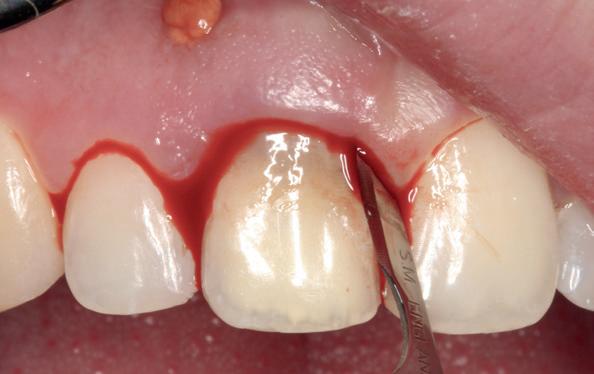

Uit het röntgenonderzoek blijkt dat op de locatie van de 22 veel bot verloren is gegaan en dat er niet direct een implantaat geplaatst kan worden. Om die reden is een botaugmentatie geïndiceerd. Wel zijn distaal van de 21 en mesiaal van de 23 de botpieken aanwezig die de papillen ondersteunen. Naast te weinig bot, is op de locatie 22 in bucco-linguale richting ook te weinig volume gingiva aanwezig. Daarom zal er tevens een soft tissue graft aangebracht worden. Tijdens deze behandeling wordt ook de recessie op de 23 zoveel mogelijk bedekt (foto 7 en 8).

Na vier maanden wordt er een CBCT gemaakt om het botvolume te kunnen beoordelen en een digitale planning te kunnen maken voor het plaatsen van het implantaat. Tevens wordt de stabiliteit van de botpieken op het buurelementen bekeken (foto 15 en 16).

Tijdens het verwijderen van het membraan is het botvolume klinisch waarneembaar en blijkt dat er voldoende bot is om het implantaat te kunnen plaat-

sen. Tijdens deze procedure wordt er ook een free gingival graft van het palatum gehaald. Deze wordt buccaal aangebracht van de 22 en 23 om zo de recessie zoveel mogelijk te bedekken en de papil tussen de 22 en 23 van meer volume te voorzien.

De flap en graft worden met poly-propelene 6.0 hechtingen gefixeerd. De tijdelijke reconstructie wordt herplaatst (foto 17-20).